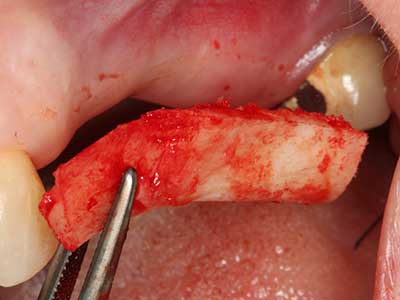

Piezosurgery has additional advantages when harvesting bone blocks. In addition to the high precision with osteotomy described above, the use of the thin saw tips specifically minimizes loss of material. Greater loss of material during harvesting can be expected with the thicker instrument tips, particularly when using Lindemann drills (Lakshmiganthan, Gokulanathan et al. 2012). The basal separation, which is necessary particularly for retromolar block transplants, is simplified by specially designed rectangular saws, with the result that piezosurgery is viewed as a precise, simple and safe procedure for harvesting retromolar bone blocks (Happe 2007) (Fig. 1-12).